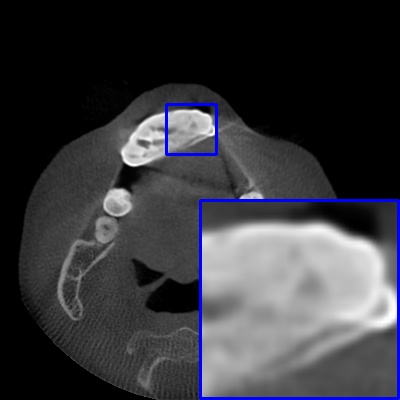

Figure 3: Visual comparison of MAR images by different methods on synthetic MA image. The PSNR (dB)/SSIM results are reported below each image for reference.

Results on synthetic MAR. In Table 1, we provide the quantitative results. One can see that our MARformer-L outperforms the other methods in terms of PSNR and SSIM, but needs only 11.76M parameters and 60.25G FLOPs. Note that the second best method Uformer-B has 50.42M parameters and 205.82G FLOPs. Besides, our MARformer-T achieves similar PSNR and SSIM results with Uformer-T, but needs only 0.40M parameters and 12.82G FLOPs compared to 5.24M and 25.39G for Uformer-T. Our MARformers also achieves faster inference speeds than the Uformers, though with inferior Dice scores, respectively. The qualitative results of visual quality are presented in Fig. 3. We observe that our MARformer-L well recovers the teeth shapes and obtains higher PSNR and SSIM results than the other comparison methods. The light-weight MARformer-L achieves similar results to Uformer-T. All these results validate that our MARformer is more efficient than the comparison methods on dental CBCT MAR.